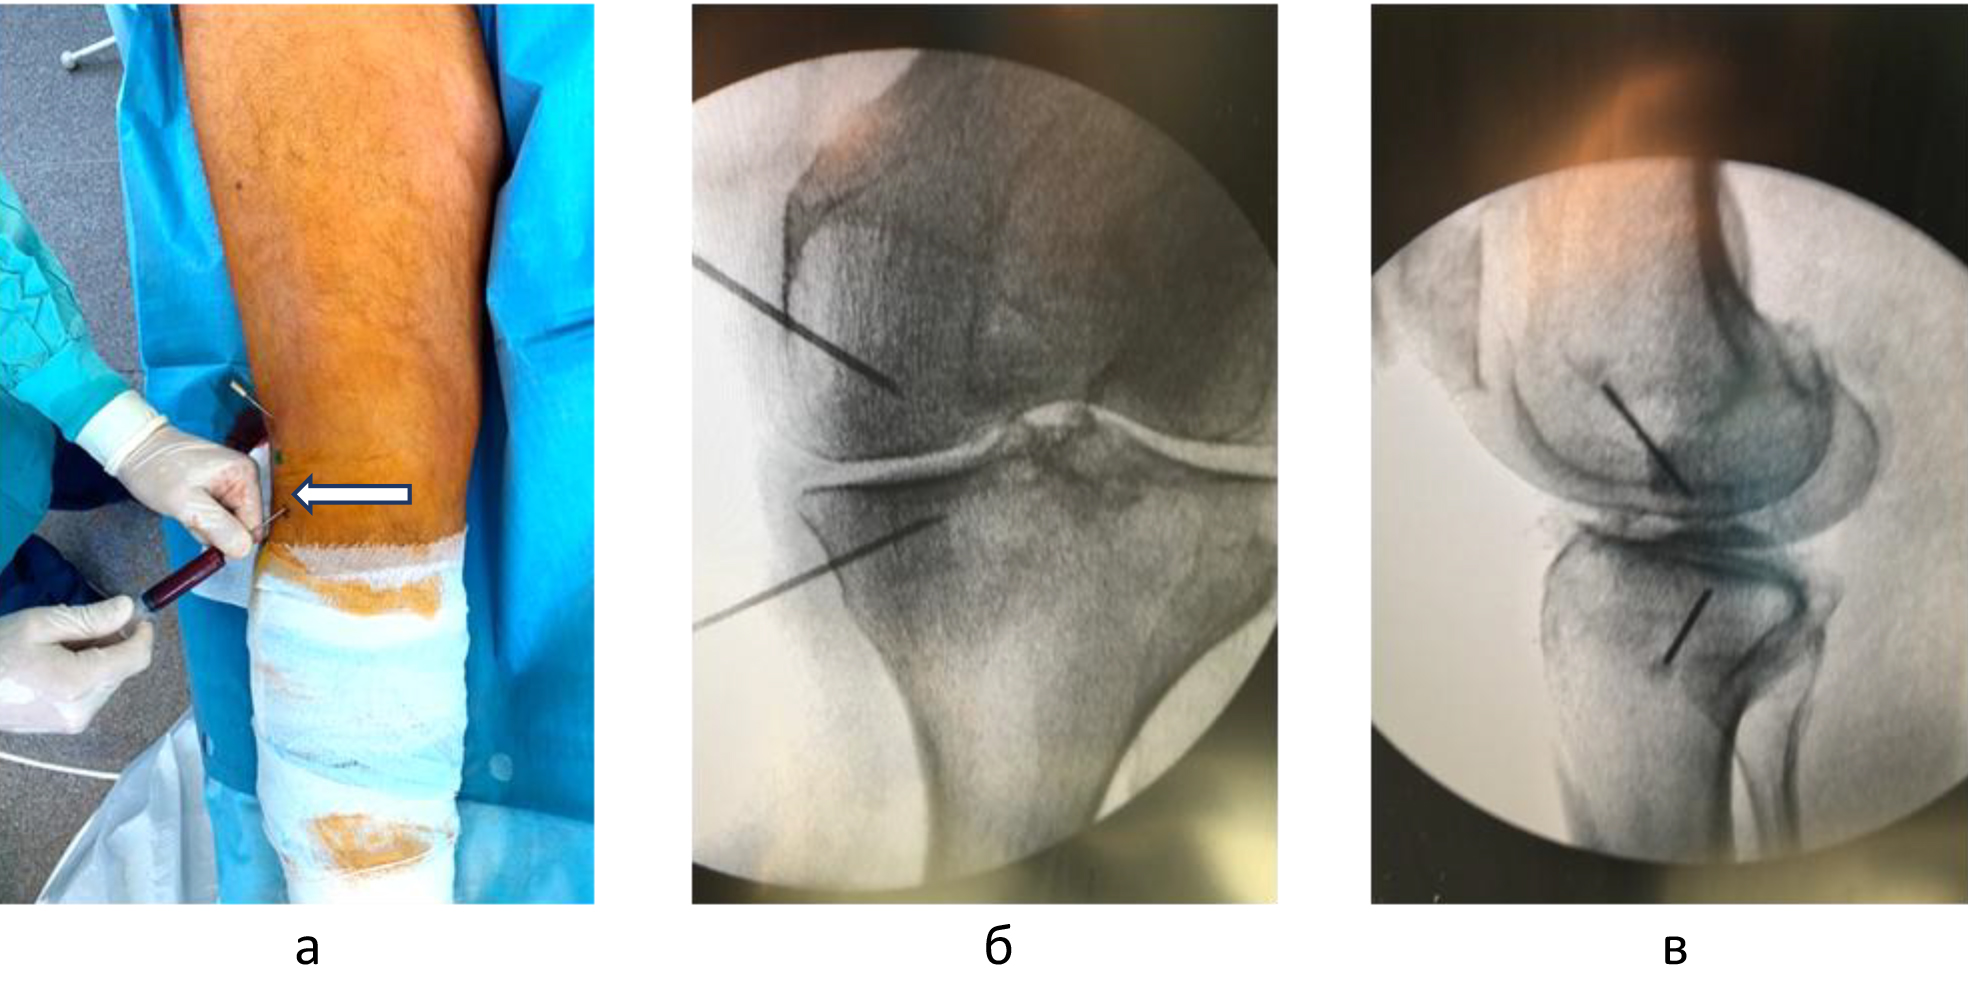

Техника подготовки препарата и инъекции. Забор крови и приготовление ОТП выполняли в условиях процедурного кабинета или перевязочной при соблюдении необходимых правил асептики и антисептики. Согласно методике YCELLBIO PRP (Корея), двухкратно центрифугировали кровь пациента и получали 3 мл ОТП, которую центрировали в узком перешейке пробирки и забирали при помощи шприца (рис. 2) Количество тромбоцитов в готовом препарате составляло 962 ± 40 × 109/л.

Внутрикостные инъекции ККМ и ОТП выполняли в условиях операционной. Используя 2%-й раствор лидокаина, инфильтрировали мягкие ткани по внутренней или наружной поверхности коленного сустава на 2 см проксимальнее и на 2 см дистальнее уровня суставной щели. Троакары вводили в кость вкручивающими движениями под углом 45 градусов по отношению к оси конечности и продвигали на глубину 1,5 см, достигнув субхондральных структур. Позиционирование троакаров оценивали с помощь электронно-оптического преобразователя (ЭОП) в 2 стандартных проекциях (рис. 3).